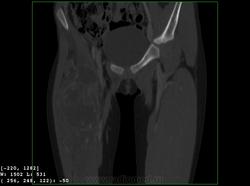

Девочка 9 лет. Родители отмечают, что 2 месяца назад девочка начала предъявлять жалобы на боли в правой пятке. Обследовались, патологии в стопе не нашли. Ребёнок постепенно начал хромать. А несколько дней назад обнаружили припухлость в в/3 бедра. Болей в бедре нет, как ночных, так и дневных. Температура не повышалась. Обратились за помощью - выполнены рентгенограммы, затем - КТ.

Злокачественная опухоль - виден луковичный периостит, инвазивный рост с лизисом кости. Но какая? Вроде бы растет из костного канала. Остеосаркома? Юинг? для этих опухолей структура какая-то больно хрящевая, мягкотканная. Хондросаркома? В таком возрасте? Почему нет клиники злокачественной опухоли кости, прежде всего - болей?

Согласна. Только периостит не луковичный, четкий лизис с козырьками Кодмена-явный признак злокачественности. А насчет болей, действительно в жизни всякое бывает, но, думаю, что ребенок не может отличить их от болей в пятке (!), а прихрамывание может быть и следствием щажения конечности.

Коллеги, давайте правильно применять термины. Периостит - окончание воспаления, применяется при остеомиелите. При опухоли - периостоз - окончание избытка, продуктивного процесса. Здесь есть "козырек Кодмена", спикулообразный периостоз, но есть так же луковичный (слоистый) периостоз, который хорошо виден на отдельных КТ-срезах. Другое дело, что для диф. диагноза опухоли (то что процесс агрессивный - сомнений не вызывыает) это, по большому счету, ничего не дает. Однако, обратите внимание на вздутие. Считаю возможны варианты телеангиоэктатической или гигантоклеточной остеосаркомы. Так же не считаю возможным исключить саркому Юинга.

Да, рентгенкартина неоднозначна, конечно, в первую очередь надо исключать зло (Юинга, остеогенную), но не уверена на 100%, что это они, спикул нет, есть луковичный периостит ниже основного очага, но это не критерий злокачественности, вздутие. Был бы возраст помладше, в первую очередь подумала бы о гистиоцитозе или туберкулезе. Еще мысли об аневризмальной кисте и ГКО. Очень хочется узнать результаты гистологии.

При такой протяженности разрушения кортикального слоя и объёме мягкотканого компонента, да и вздутии кости, что здесь может быть кроме Зла? Однако гистология интересна.

Вы правы, коллега, мне тоже видятся уровни. Но если АКК, откуда периостоз? По КТ его оспорить сложно... По скиалогии, локализации наиболее подходит гигантоклеточная опухоль, тем более, что она часто сочетается с вторичной аневризмальной кистой. Но возраст?! хотя, чего сейчас только не бывает...